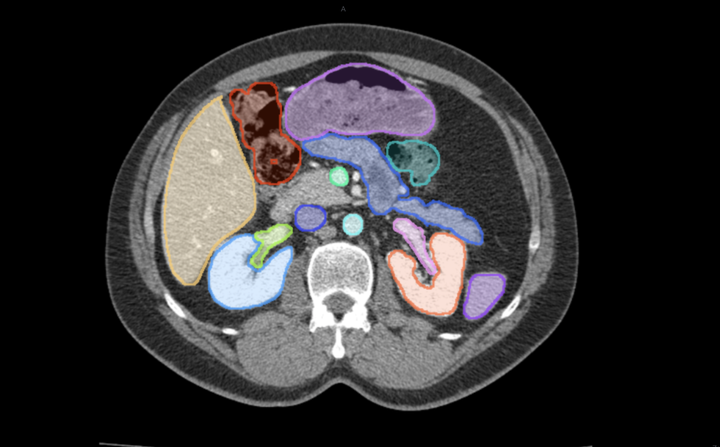

腹腔器官标注

医学影像具有特殊性和复杂性,不同于日常的二维图像,医学影像都是三维数据,目标对象的边缘时常不够清晰,分割难度大,专业性强。基于这些特点,东软智能医疗科技研究院通过深入研究在医学影像领域预训练大模型技术,通过“预训练大模型+下游任务微调”的方式,有效地从大量标记和未标记的数据中捕获知识,扩展模型的泛化能力,解决了模型碎片化问题,为人工智能+医疗提供了崭新的技术路线,为突破现有算法性能的瓶颈提供了无限可能。同时,结合了东软自身积累的多种多样的带有标注数据的大量数据集,对预训练大模型进行二次训练,并针对医学影像的三维特点进行优化,推出了医学影像分割大模型MISM,进一步提高了医学影像标注的质量和效率。

飞标平台借助医学影像分割大模型MISM进行了全新升级,4.0版实现了通过一个点、一个边界框,一键分割出病灶或解剖结构的功能,能够更精准的连续逐层标注。此外,飞标4.0版支持集成第三方的预标注算法,使飞标平台具有了功能可扩展的开放性。

1、提供像素级精准标注,提升精准性——提供基于像素级的标注工具,标注精度可达到1像素。还可对疑似病灶进行自动预标注,减少漏标、误标情况。

2、提供高效自动化工具,提高标注效率——结合影像组学算法、人工智能模型,集成了大量的自动、半自动标注工具,通过影像自身特征和智能模型双重计算,快速识别标注内容和边界,从而大幅提高效率。

3、智能化工具,加速全流程——通过大量智能化、自动化工具加快医学标注工作全流程的整体效率,包括影像预标注、标注工具智能化、标注结果自动优化。

4、自动标注+人工审核,加速高质量标注数据集落地——自动勾画、半自动勾画、手工勾画相结合,实现自动检测病灶、自动分割病灶、结合人工介入的审核优化构建,高质量标注数据集,加速医疗影像智能模型落地应用。

5、高级可视化,提高标注效率和准确率——通过大量的基于web的三维可视化技术,让使用者从二维标注扩展到全面了解病变情况的三维环境,并提供基于三维立体交互式分割技术,让标注更智能。